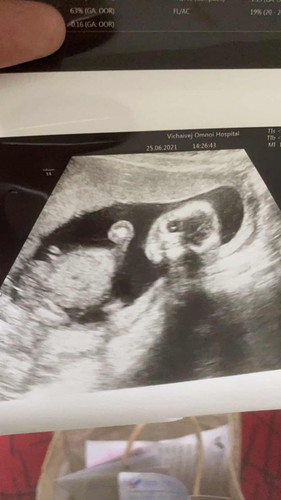

ท้องแรก 16 สัปดาห์

สอบถามหน่อยค่ะแม่ๆ อายุครรภ์16สัปดาห์ น้องอยู่ในท่านอนคว่ำแบบนี้ปกติไหมคะ คุณหมอไม่ได้แจ้งหรือบอกอะไร ขอบคุณล่วงหน้าค่ะ😊